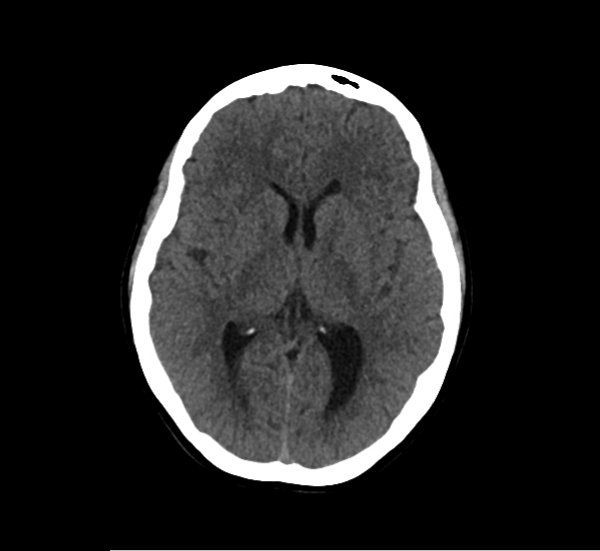

CT Brain Anatomy